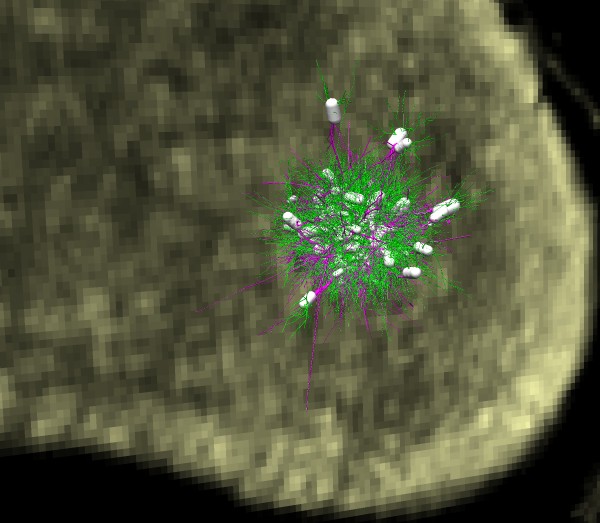

| Neuron trace

| 500 neurons, spread out

| Physiological density.

- Show a traced neuron superimposed on 20 um plane.

- Show 500 traced neurons at 10x normal spacing.

- Show 500 neurons at normal spacing, densely packed.